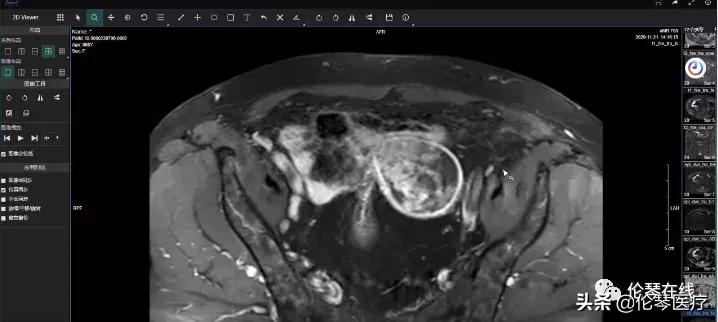

今天伦琴医疗和大家分享腹部子宫占位的鉴别诊断病例。

病例分析视频截图如下

上期病例答案公布——子宫癌肉瘤